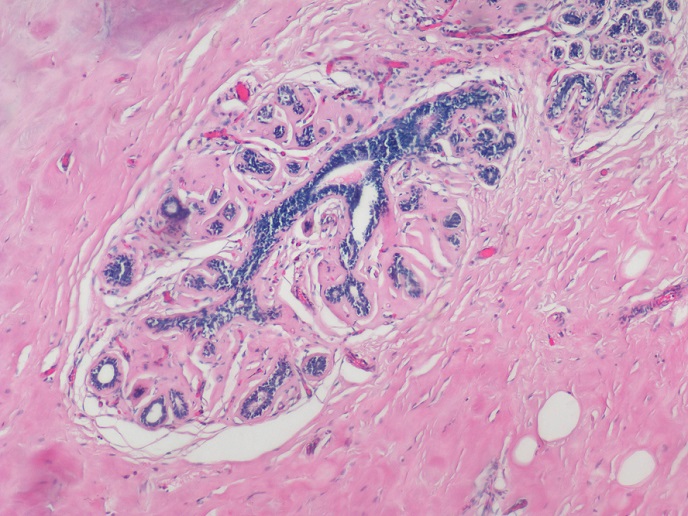

明美生物顯微鏡搭載高分辨率MSX2相機(jī),可清晰呈現(xiàn)HE染色病理切片的細(xì)胞細(xì)節(jié)(如乳腺癌樣本中藍(lán)色的細(xì)胞核與紅色的胞質(zhì)),幫助快速識(shí)別癌細(xì)胞形態(tài)特征,為精準(zhǔn)診斷提供可靠依據(jù)。

明美生物顯微鏡搭配msx2拍攝HE染色的乳腺癌病理切片,紅色為胞質(zhì),藍(lán)色為染色體